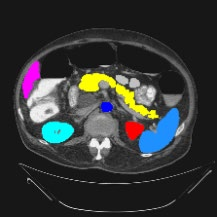

Transformers have made remarkable progress towards modeling long-range dependencies within the medical image analysis domain. However, current transformer-based models suffer from several disadvantages: (1) existing methods fail to capture the important features of the images due to the naive tokenization scheme; (2) the models suffer from information loss because they only consider single-scale feature representations; and (3) the segmentation label maps generated by the models are not accurate enough without considering rich semantic contexts and anatomical textures. In this work, we present CASTformer, a novel type of generative adversarial transformers, for 2D medical image segmentation. First, we take advantage of the pyramid structure to construct multi-scale representations and handle multi-scale variations. We then design a novel class-aware transformer module to better learn the discriminative regions of objects with semantic structures. Lastly, we utilize an adversarial training strategy that boosts segmentation accuracy and correspondingly allows a transformer-based discriminator to capture high-level semantically correlated contents and low-level anatomical features. Our experiments demonstrate that CASTformer dramatically outperforms previous state-of-the-art transformer-based approaches on three benchmarks, obtaining 2.54%-5.88% absolute improvements in Dice over previous models. Further qualitative experiments provide a more detailed picture of the model's inner workings, shed light on the challenges in improved transparency, and demonstrate that transfer learning can greatly improve performance and reduce the size of medical image datasets in training, making CASTformer a strong starting point for downstream medical image analysis tasks.